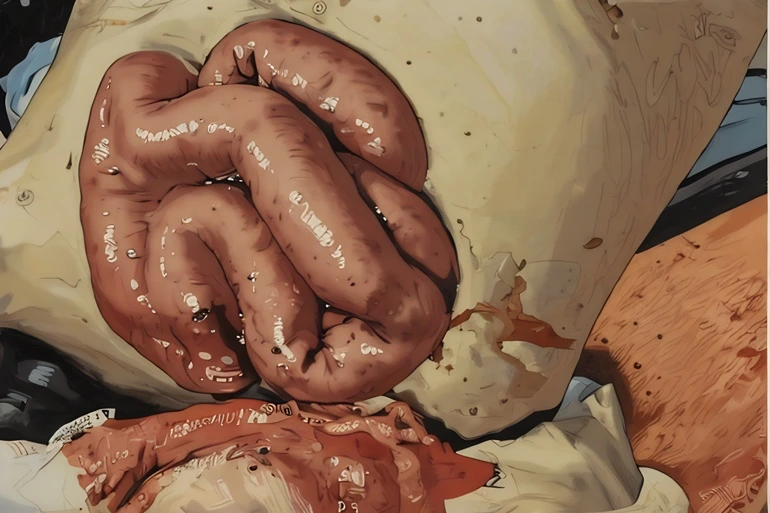

→Image at top is an artistic rendering from a 14-year-old boy who sustained a penetrating injury to his abdominal wall after impacting the handlebars of his bike. Note the bowel perforation at approximately 7 o’clock on the bowel. This should not be reduced, as it will spill bowel contents into his abdomen. 5

If there is a rupture or leakage of the bowel contents, no attempt should be made to reduce the evisceration as that would just spill bowel contents into the abdomen, all but ensuring significant intra-abdominal infection. Similarly, if any associated bowel bleeding can’t be controlled, that too is a contraindication to reduction.4